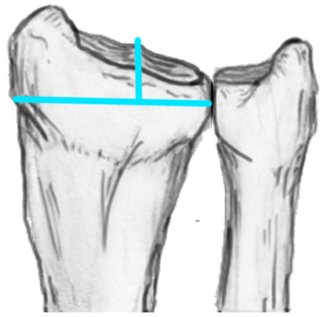

Distal Radius Angles

- radial volar tilt 11°

- radial inclination 22°

- radius is 11 mm longer than ulna

- ulna variance 2mm positive on average